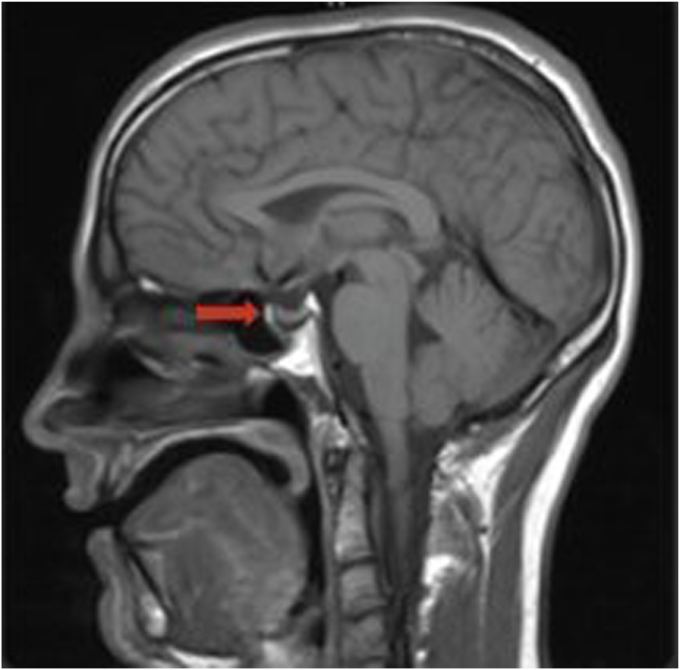

The patient was a 31-year-old man with history of CF who was referred to endocrinology clinic for the evaluation of hypogonadism. Serum testing revealed a total testosterone of 175 ng/mL (296-1377), luteinizing hormone 2.8 mIU/mL (1.2-8.6), and a prolactin of 341 ng/mL (3-13). A brain magnetic resonance imaging was obtained, which revealed a 1 cm hypoenhancing left sellar lesion. He was started on cabergoline. His testosterone increased to 707 ng/dL after a year on cabergoline treatment. His prolactin decreased to 12 ng/mL after a year of treatment. The pituitary adenoma decreased 50% in size 2 years after cabergoline was initiated.